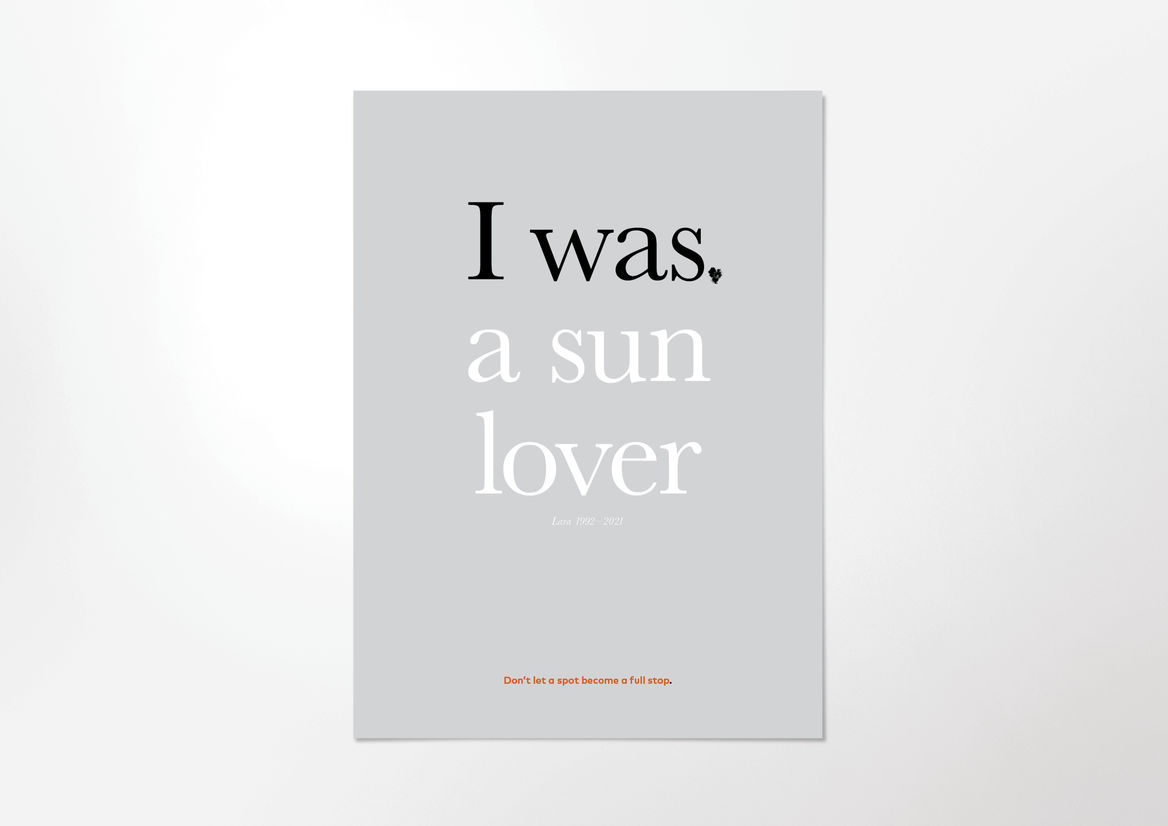

The Melanoma Typeface is a font that taught an entire nation to take a second look at their spots.

We created a usable font, made up of seven glyphs of a single character - the full stop. Each glyph was designed in partnership with New Zealand medical professionals to accurately represent one of the visual symptoms of Melanoma. When viewed at a small size, the glyphs all look like slightly misshapen full stops. But as point size increased, more and more detail is revealed in each character, until the true nature of each spot is impossible to ignore.

These seven simple characters could turn any piece of design or messaging into a melanoma awareness campaign, simply by swapping out their full stop for ours.

Our Melanoma Typeface transformed regular communications into an educational piece, showing the public that a cancerous spot can hide in plain sight.